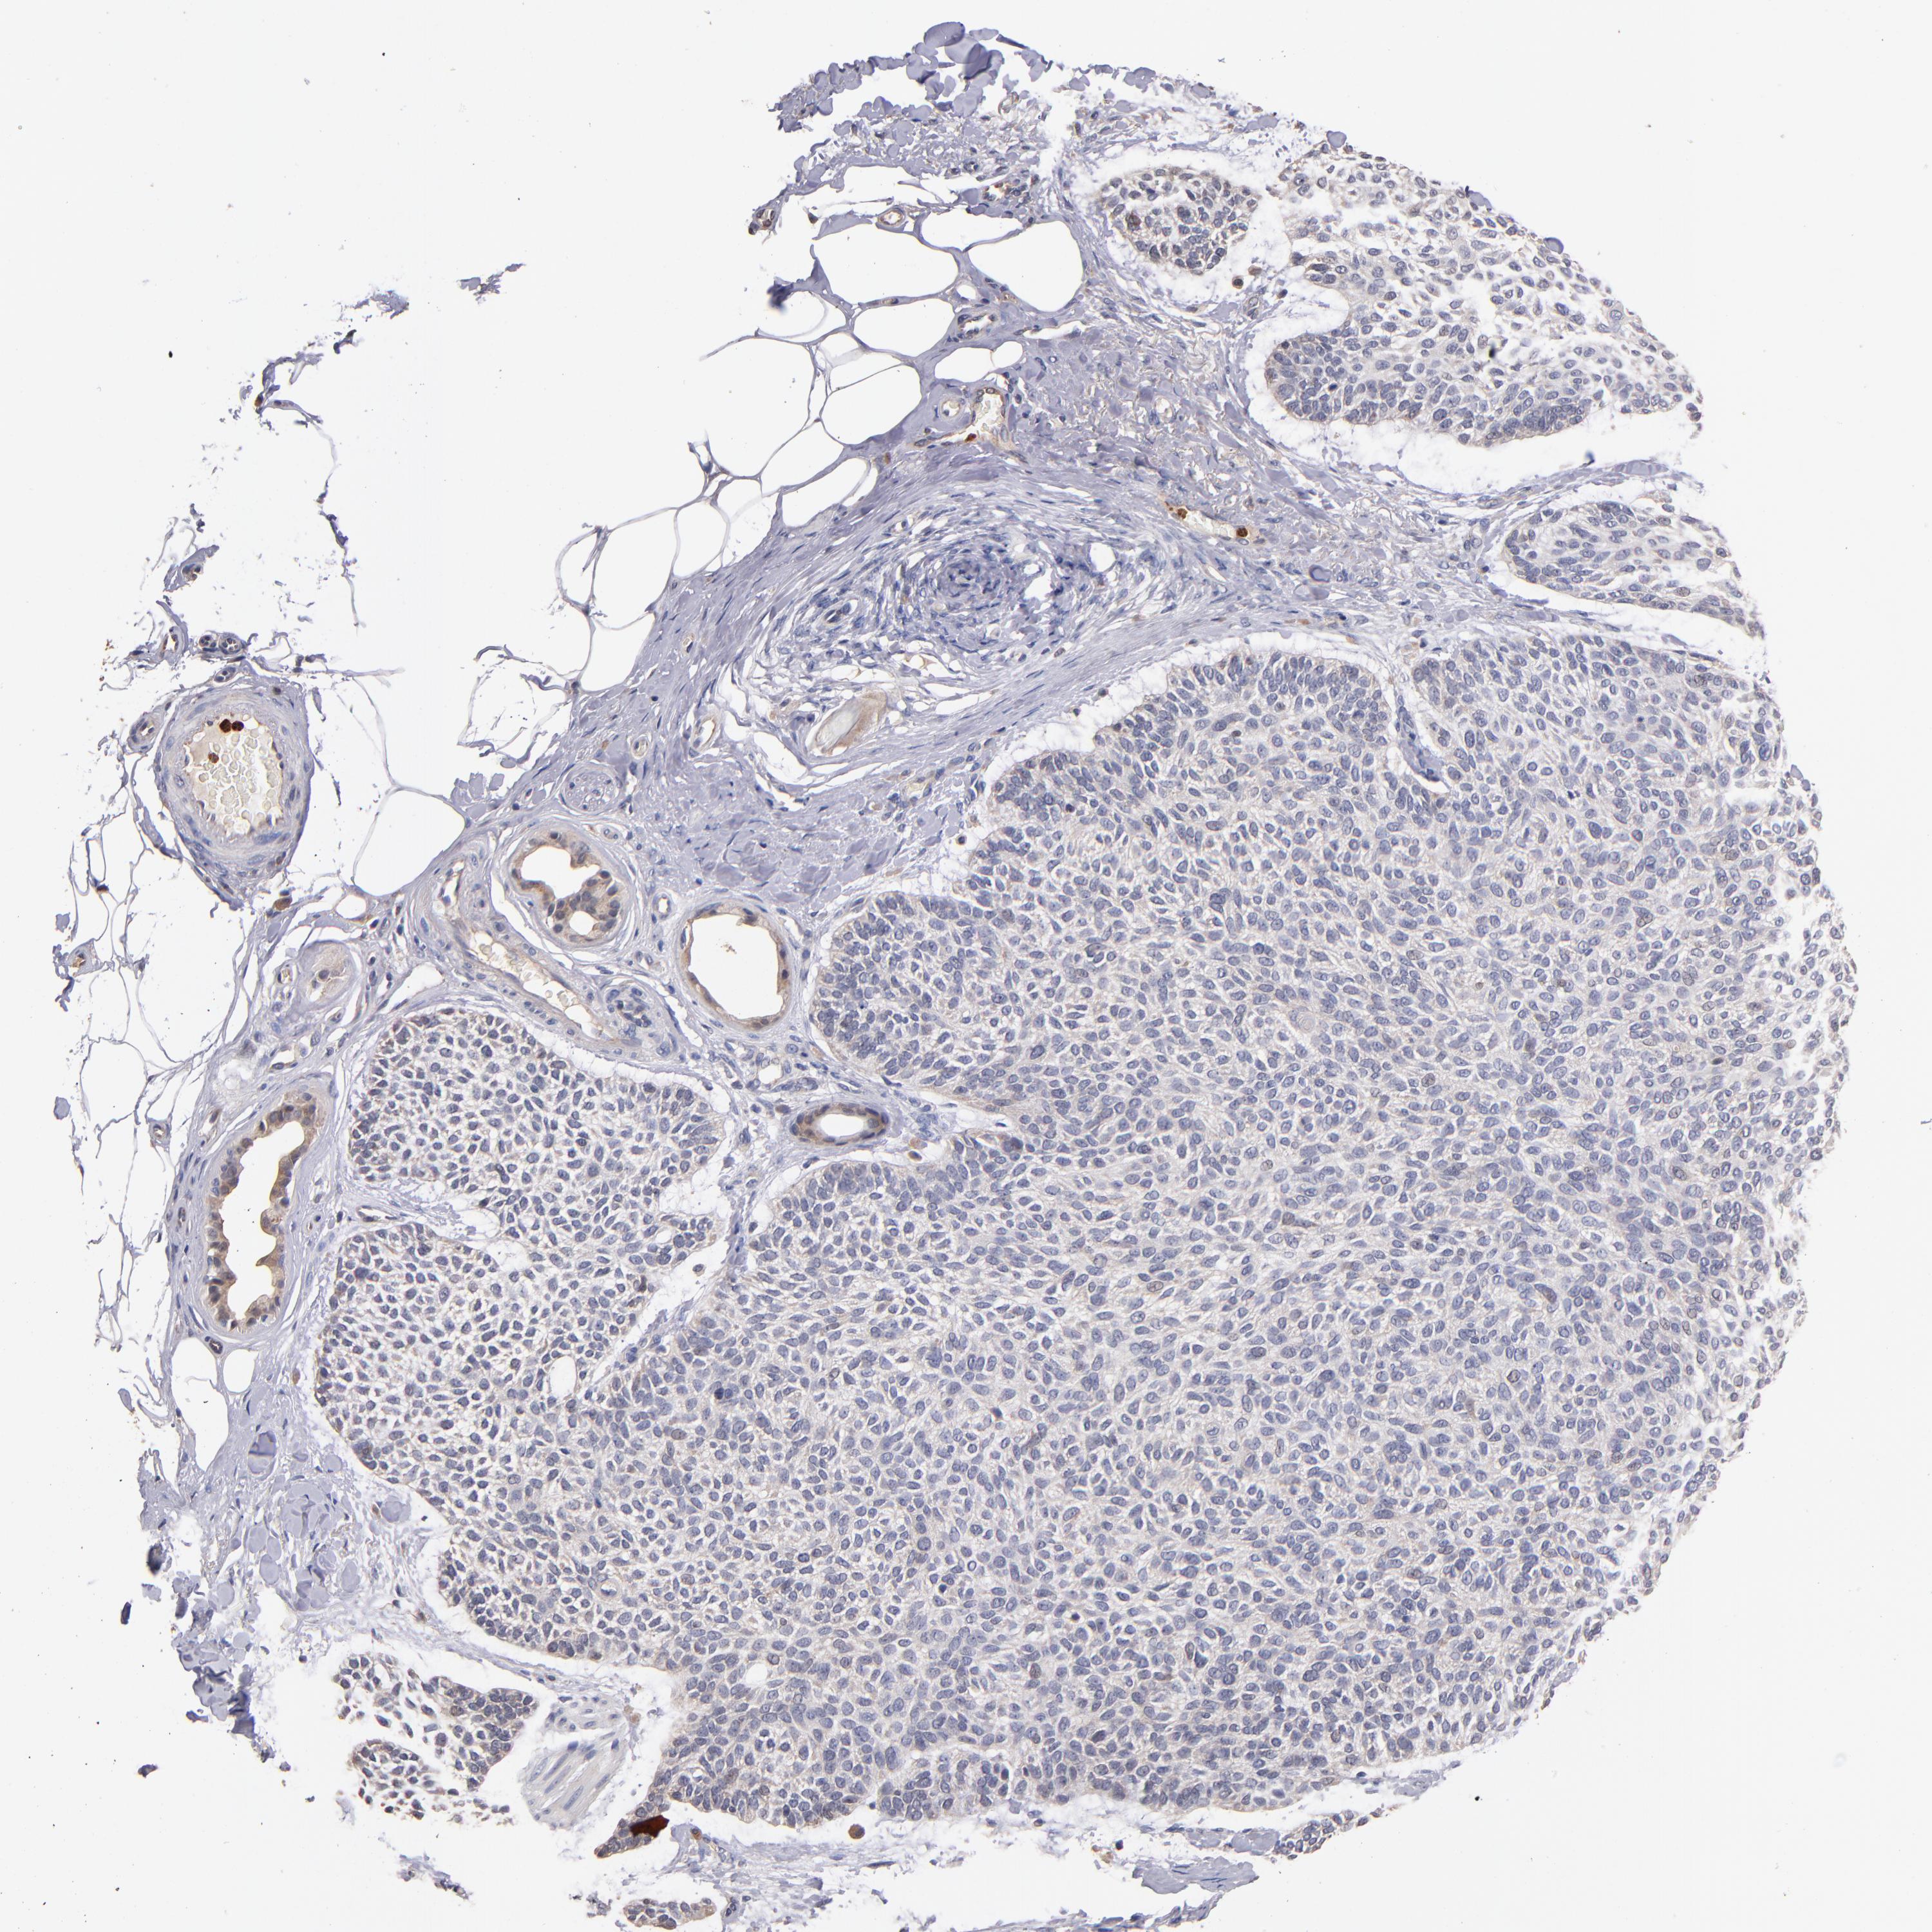

SKIN CANCER - Protein expressioni

A mouse-over function shows sample information and annotation data. Click on an image to view it in a full screen mode. Samples can be filtered based on level of antibody staining by selecting one or several of the following categories: high, medium, low and not detected. The assay and annotation is described here.

Each image is clickable and will lead to virtual microscopy that enables deeper exploration of all samples and also displays staining intensity scores, fraction scores and subcellular localization as well as patient and tissue information for each sample.

Antibody HPA003054

Squamous cell carcinoma, NOS